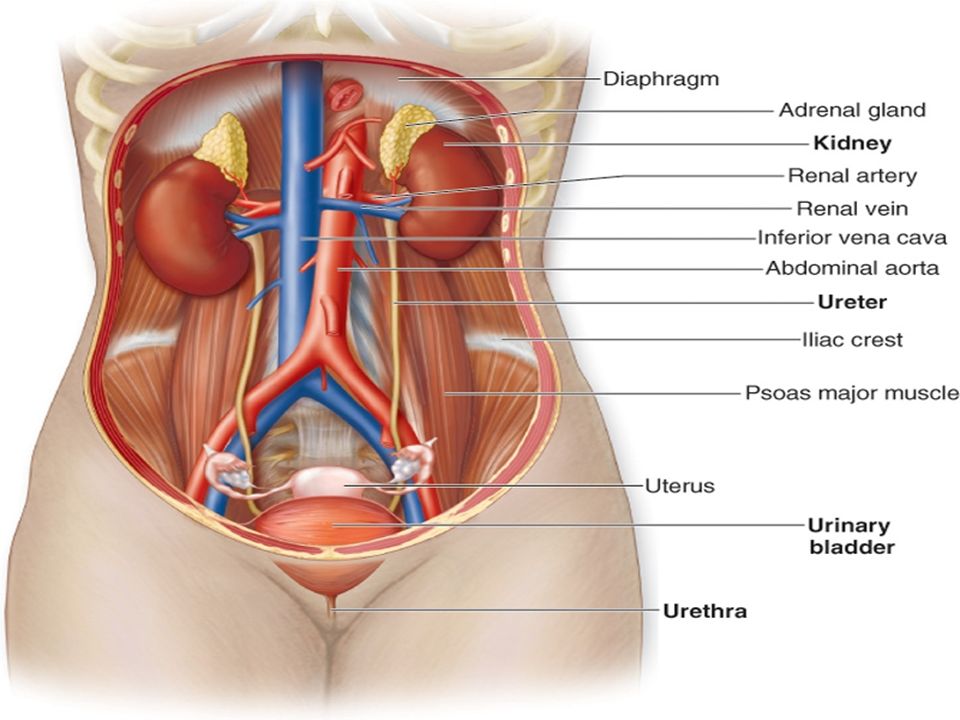

The kidneys are 11 centimeters long paired reddish brown organs situated on the posterior wall of the abdominal cavity one on each side of the vertebral column and capped by the adrenal gland. H ions are produced as a natural byproduct of the metabolism of dietary proteins and accumulate in the blood over time. Connective tissue anchors the kidneys to surrounding structures and helps maintain their normal position.

Upper portions of the kidneys are somewhat protected by the eleventh and twelfth ribs figure 1. Anatomy of the kidneys. Each kidney weighs about 125175 g in males and 115155 g in females.

Due to the presence of the liver the right kidney is slightly lower than the left kidney. They are about 1114 cm in length 6 cm wide and 4 cm thick and are directly covered by a fibrous capsule composed of dense. Anatomy of the urinary system.

The kidneys monitor and regulate the levels of hydrogen ions h and bicarbonate ions in the blood to control blood ph. Glomerular filtration glomerular filtration is the renal process whereby fluid in the blood is filtered across the capillaries of the glomerulus. The right kidney is lower than the left due to displacement by the liver.